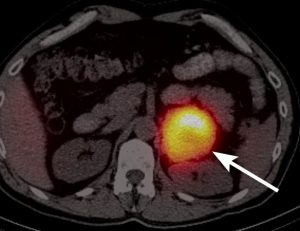

- Χρήσιμο θεωρείται και το σπινθηρογράφημα με 131 Ι- μεταϊωδοβενζυλγουανιδίνη-MIBG/metaiodobenzylguanidine/ σπινθηρογράφημα (καλύτερα να μη γίνεται)

- Ακόμα λεπτομερής εντοπισμός μπορεί να ληφθεί με σάρωση ΡΕΤ χρησιμοποιώντας PET/CT-Positron Emission Tomography/Computed TomographyΤομογραφία Εκπομπής Ποζιτρονίων/Αξονική Τομογραφία με F-18-fluorodopamine (καλύτερα να μη γίνεται)